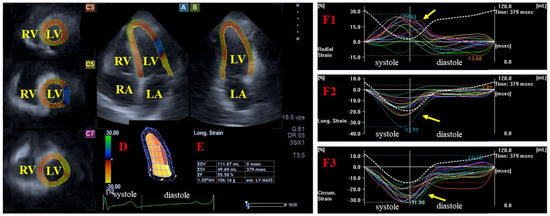

Introduction. The etiology of cardiac amyloidosis (CA) involves the systemic or localized deposition of misfolded amyloid proteins within the myocardial interstitium and valvular structures. The primary objective of this study was to employ three-dimensional speckle-tracking echocardiography (3DSTE) to perform a detailed analysis of [...] Read more.

Introduction. The etiology of cardiac amyloidosis (CA) involves the systemic or localized deposition of misfolded amyloid proteins within the myocardial interstitium and valvular structures. The primary objective of this study was to employ three-dimensional speckle-tracking echocardiography (3DSTE) to perform a detailed analysis of the aortic valve annulus (AVA) and left ventricular (LV) strains in CA patients and to compare these parameters with those of matched healthy controls. Methods. The initial cohort for this study comprised 35 individuals diagnosed with CA. However, 12 patients were subsequently excluded from the final analysis due to suboptimal image quality precluding accurate measurement of AVA dimensions and/or LV strains. The final analytical group, therefore, consisted of 23 CA patients (14 males), with a mean age of 64.6 ± 7.1 years. The results obtained from the CA patient group were compared with those of a healthy control cohort comprising 23 individuals (14 males; mean age: 53.2 ± 5.3 years). Results. In CA patients, AVA area was greater in end-diastole in 11 out of 23 cases (48%), and in end-systole in 8 out of 23 cases (35%), while it proved to be equal in 4 out of 23 cases (17%). The ratio of healthy controls with greater end-diastolic AVA area (12 out of 23, 52%) and greater end-systolic AVA area (11 out of 23, 48%) did not differ from that of CA patients. End-diastolic and end-systolic maximum and minimum AVA diameters, areas and perimeters did not differ between CA patients and matched controls. AVA plane systolic excursion (AAPSE) was found to be significantly impaired in all CA patients irrespective of AVA area size. Basal LV radial (RS), circumferential (CS) and longitudinal (LS) strains were reduced in CA patients compared with those of controls. End-systolic AVA dimensions tended to be reduced in CA patients with greater end-diastolic AVA area compared with those with greater end-systolic AVA area. While basal LV-RS and LV-CS proved to be similar between CA subgroups, basal LV-LS tended to be higher in CA patients with greater end-systolic AVA area. Controls with greater end-diastolic AVA area showed lower basal LV-RS and LV-LS compared with those with greater end-systolic AVA area. CA patients with equal end-diastolic and end-systolic AVA area (n = 4) showed similarly reduced AAPSE, basal LV-RS, basal LV-CS and LV-LS. Conclusions. In the presence of CA, the AVA is not dilated; however, its spatial displacement is reduced, suggesting its functional impairment, as represented by AAPSE, possibly due to the reduction in all concomitant LV strain parameters. Full article